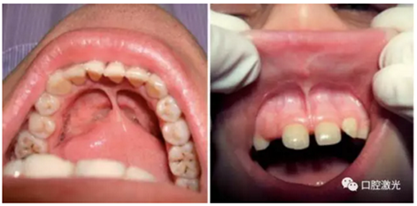

口腔系带整形是口腔外科手术中较为常见的手术,一般包括对唇系带和舌系带的延长、整形。其中,唇系带整形通常在口腔正畸中有广泛的应用。半导体口腔激光拥有便携性强、结构紧凑、效率高等特点,能有效杀灭口腔细菌和对血液、软组织起到凝固的作用。半导体口腔激光的波长通常是810nm至980nm,可以使用连续模式或者脉冲模式,采用接触或非接触的治疗手柄。

利用口腔激光进行系带整形需要实施局麻,可以使用2%利多卡因。采用300um激光光纤,设置功率为4W。激光光纤垂直和水平作用于系带上,从而使系带黏膜得到很好的分离。通过这种方式,系带在水平方向上可以很容易获得一个较深的切口。系带整形后的伤口是呈菱形,整个过程大约4,5分钟。在任何情况下,都不需使用缝针。可以使用冰敷的方式降低组织温度,控制组织坏死的风险。术后复检的时间为1周、3周和3个月。复检时,包括疼痛,出血,水肿,疤痕组织形成以及伤口愈合的特征都应得到有效的评估。

在术中和术后恢复期间,都没有观察到出血的情况。术后没有发现明细的疼痛和水肿。术后三周时,口腔黏膜完全恢复健康,没有形成疤痕组织。在长期跟踪观察中,口腔黏膜的色泽和形态一直处于正常状态。

由此可见,利用口腔激光进行系带整形在口腔外科手术中可以大大降低传统手术方式的不足。激光外科手术的优势在于:更高的手术精度以及更小的疼痛感、出血、水肿和结疤的可能性。整个手术过程迅速、安全和操作简单,术后无需缝合,因此可以在门诊中实施。并且,患者对手术结果的满意度极高。